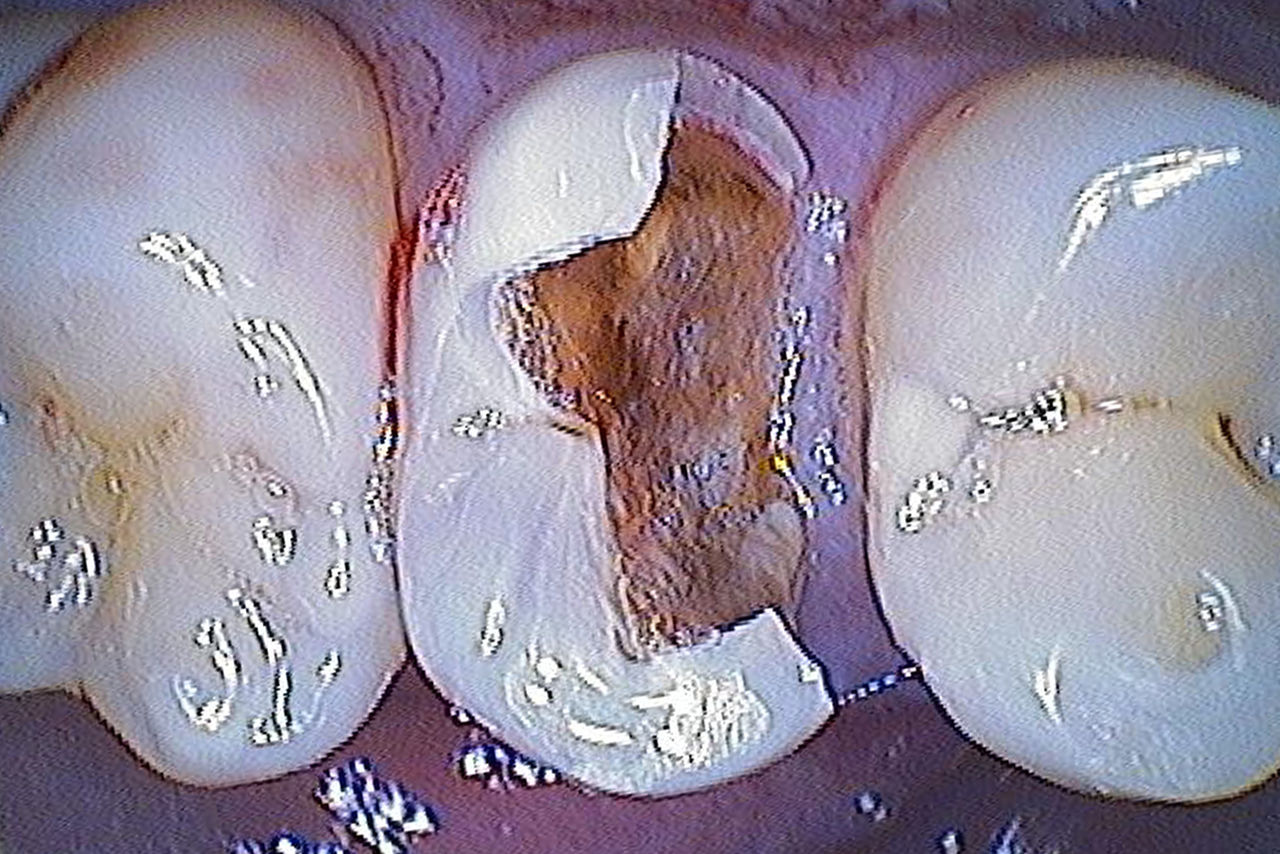

Before: A large carious mesial lesion on tooth 15. The tooth showed asymptomatic apical periodontitis and a significant loss of tooth structure.

After: Chairside-fabricated restoration made of CEREC MTL Zirconia designed using the Biogeneric individual function in the CEREC Software.